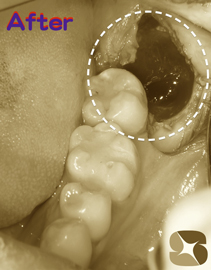

歯肉と骨、そして舌(歯並びが内向きなため)に囲まれていた親知らずの歯。かなり難しい抜歯でしたが無事に終わりました。

CT画像で抜歯のシュミレーション(準備)が事前にできていたことが、短い時間の施術につながりました。